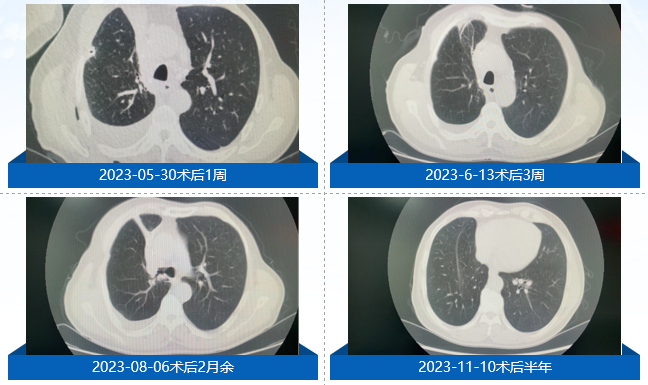

随访结果:术后1周、3周、2月、半年、1年、1.5年复查CT,未见复发征象。截至目前,患者DFS(无病生存期)已达24个月。